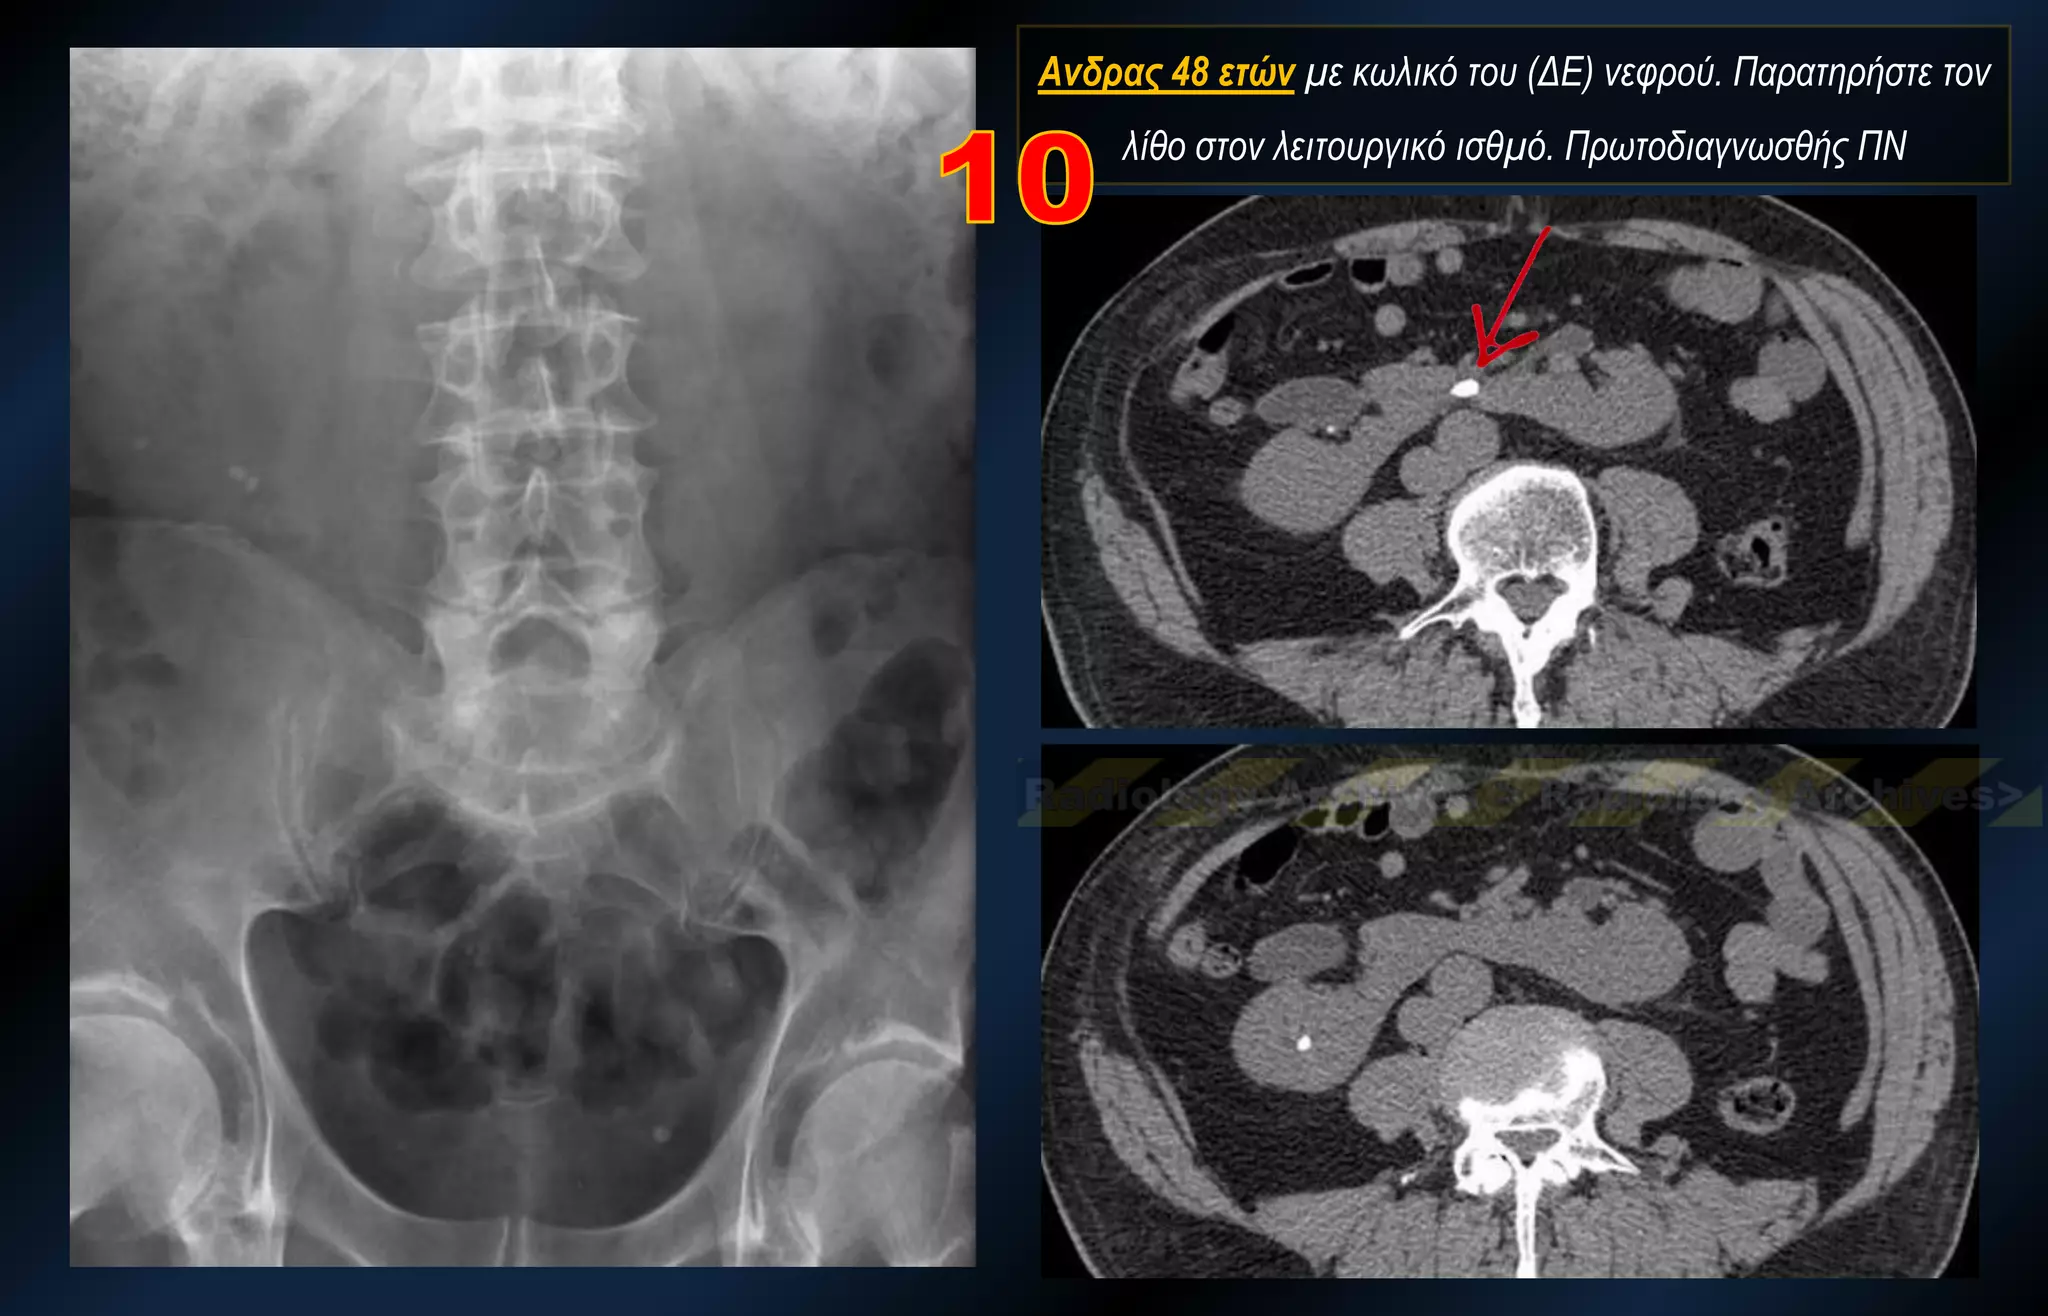

Ανδρας 48 ετών με κωλικό του (ΔΕ) νεφρού. Παρατηρήστε τον λίθο στον λειτουργικό ισθμό. Πρωτοδιαγνωσθής ΠΝ

Ανδρας 48 ετώνμε κωλικό του (ΔΕ) νεφρού. Παρατηρήστε τον λίθο στον λειτουργικό ισθμό. Πρωτοδιαγνωσθής ΠΝ